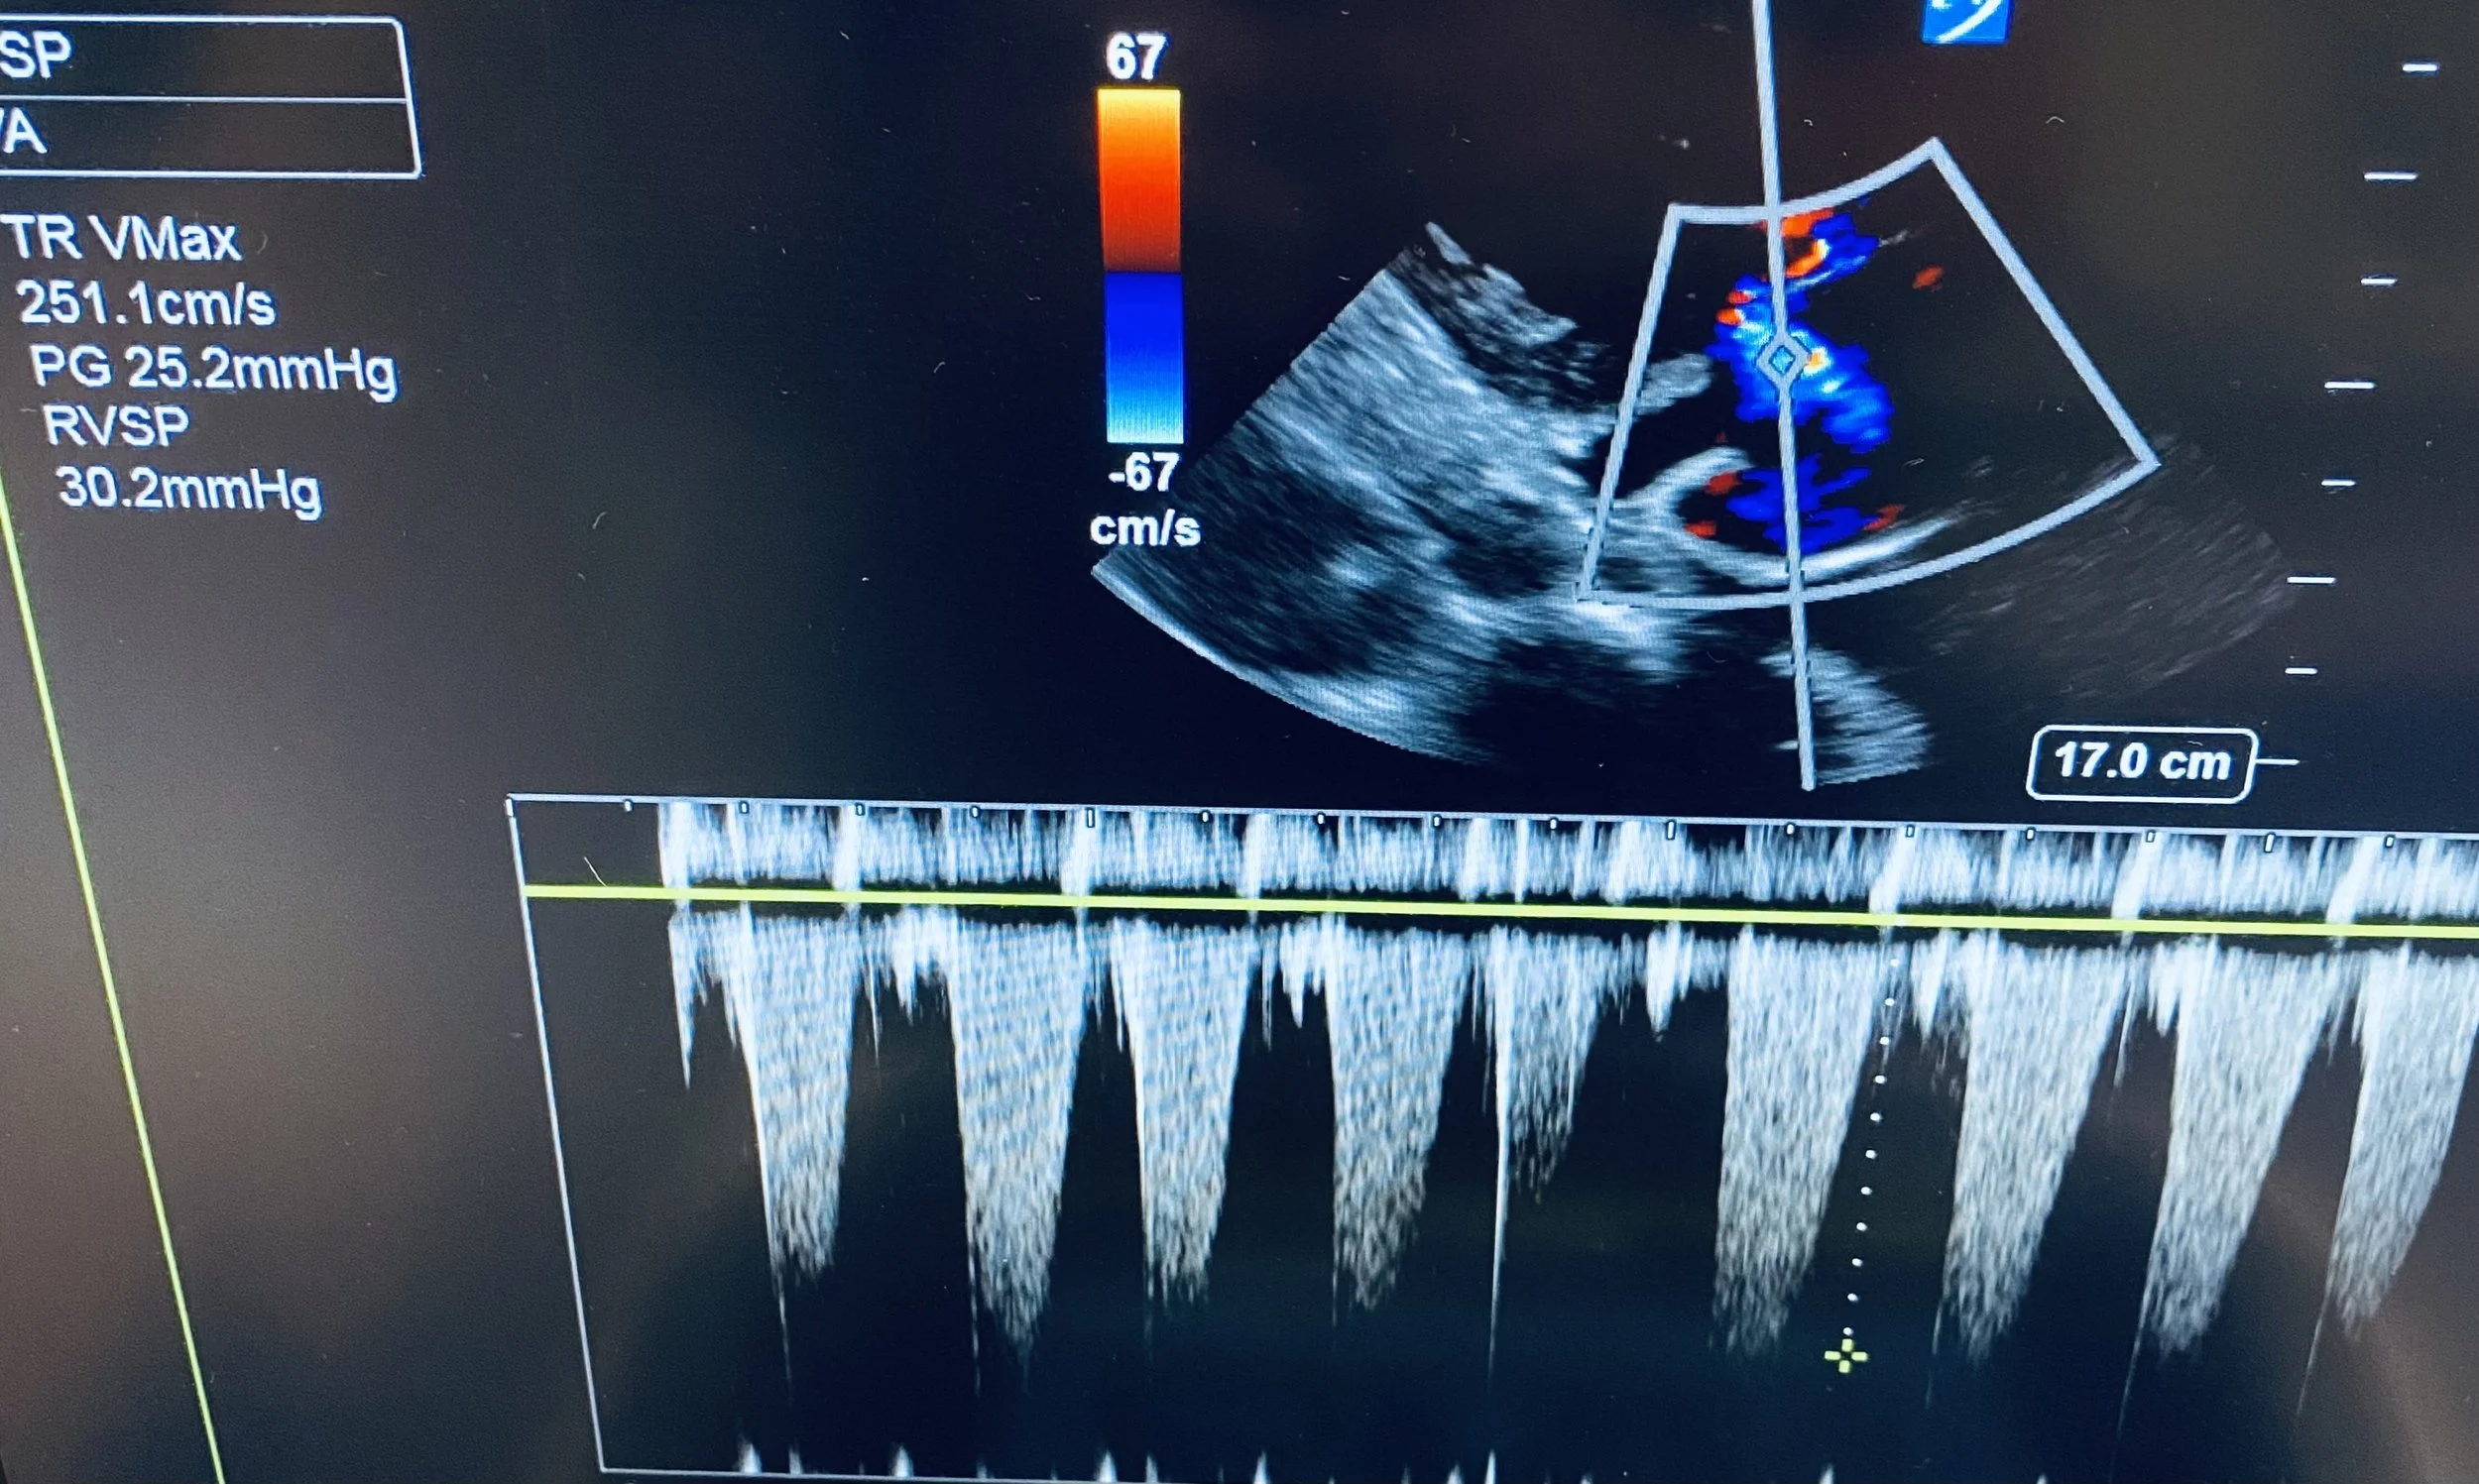

• Place CW doppler through the TR to obtain a parabolic TR jet as seen in the still above.

• Most ultrasound machines will have an option for ‘TR Vmax’ - use this to mark the bottom of the parabola and the RVSP will be calculated automatically.

In the top picture the TR Vmax was 251cm/s which corresponds to an RVSP of 30.2mmHg

In atrial fibrillation there will be beat to beat variation, so it is important to either take several measurements, or to pick a representative ‘average’ beat.